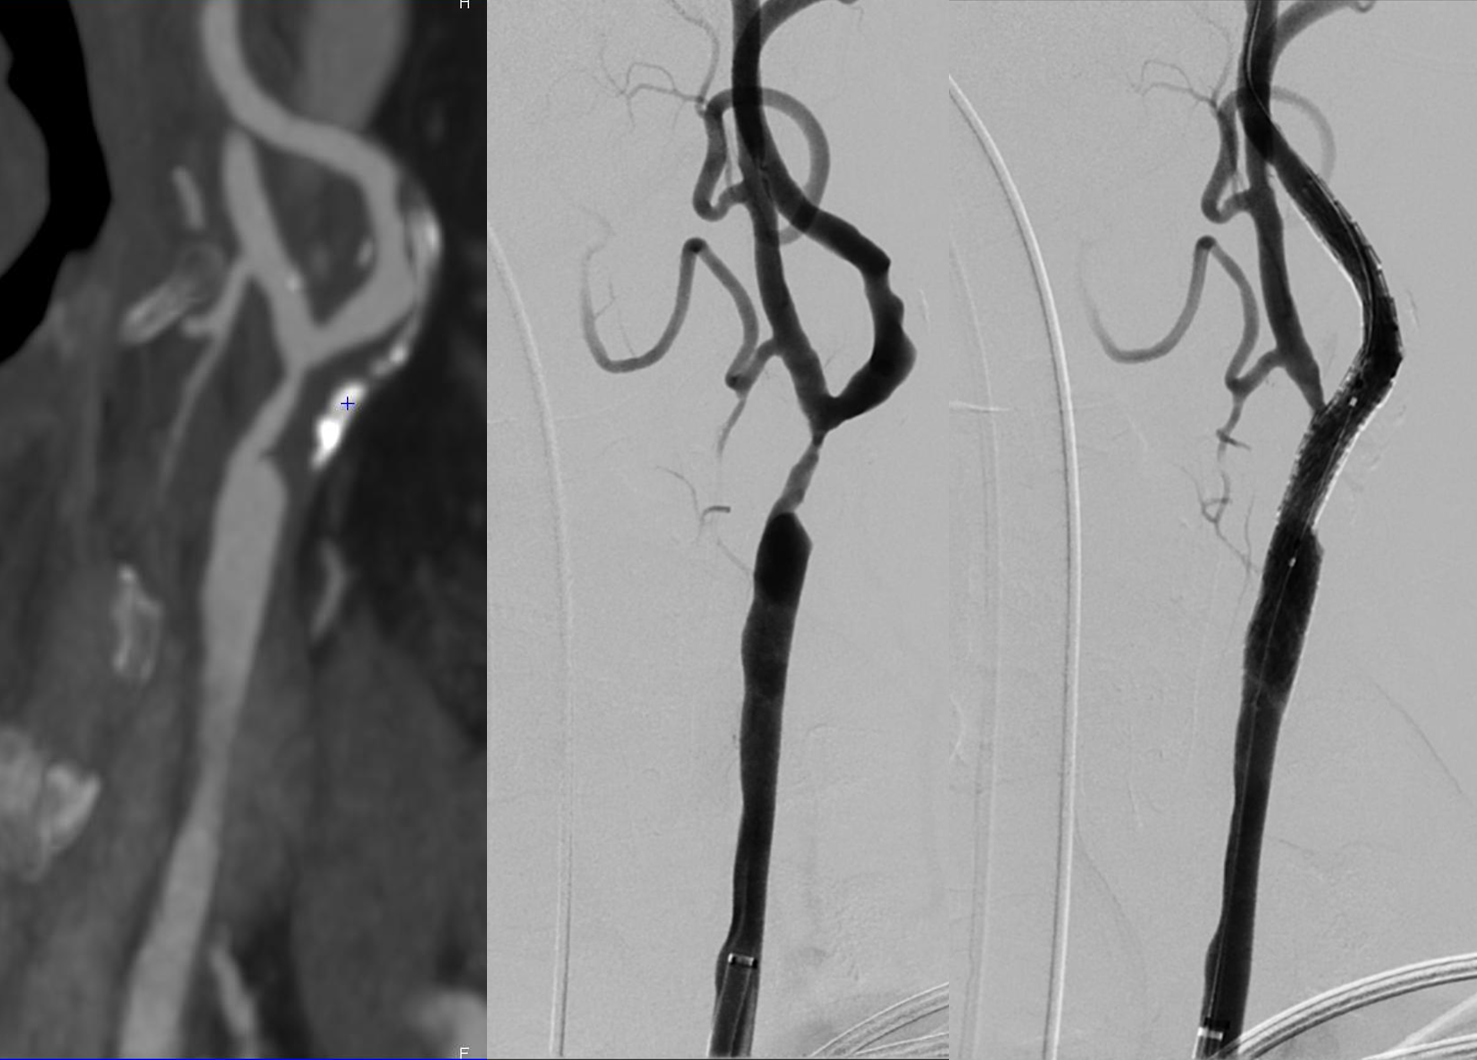

Après une ponction artérielle (piqûre), un cathéter (petit tuyau souple) est introduit soit dans l’artère fémorale commune droite au niveau du pli de l’aine soit dans l’artère radiale au niveau du poignet. Un cathéter est ensuite dirigé en temps réel sous guidage radiologique vers l’artère carotide pathologique. Une cartographie des artères carotides (artériographie) est alors réalisée en injectant du produit de contraste par le cathéter afin de bien évaluer l’étendue et le degré de rétrécissement de la carotide et réaliser ainsi un planning opératoire précis (zone d’inflation du ballon et de mise en place du stent).

On passe alors la sténose (rétrécissement) avec le cathéter puis on réalise alors soit directement la mise en place du stent (angioplastie stenting), soit il est parfois nécessaire réaliser une prédilatation au ballon (angioplastie au ballon) avant de mettre en place le stent. On réalise enfin une dernière artériographie pour confirmer la bonne efficacité de l’intervention. L’anesthésie est alors diminué et le patient est transféré en salle de réveil.